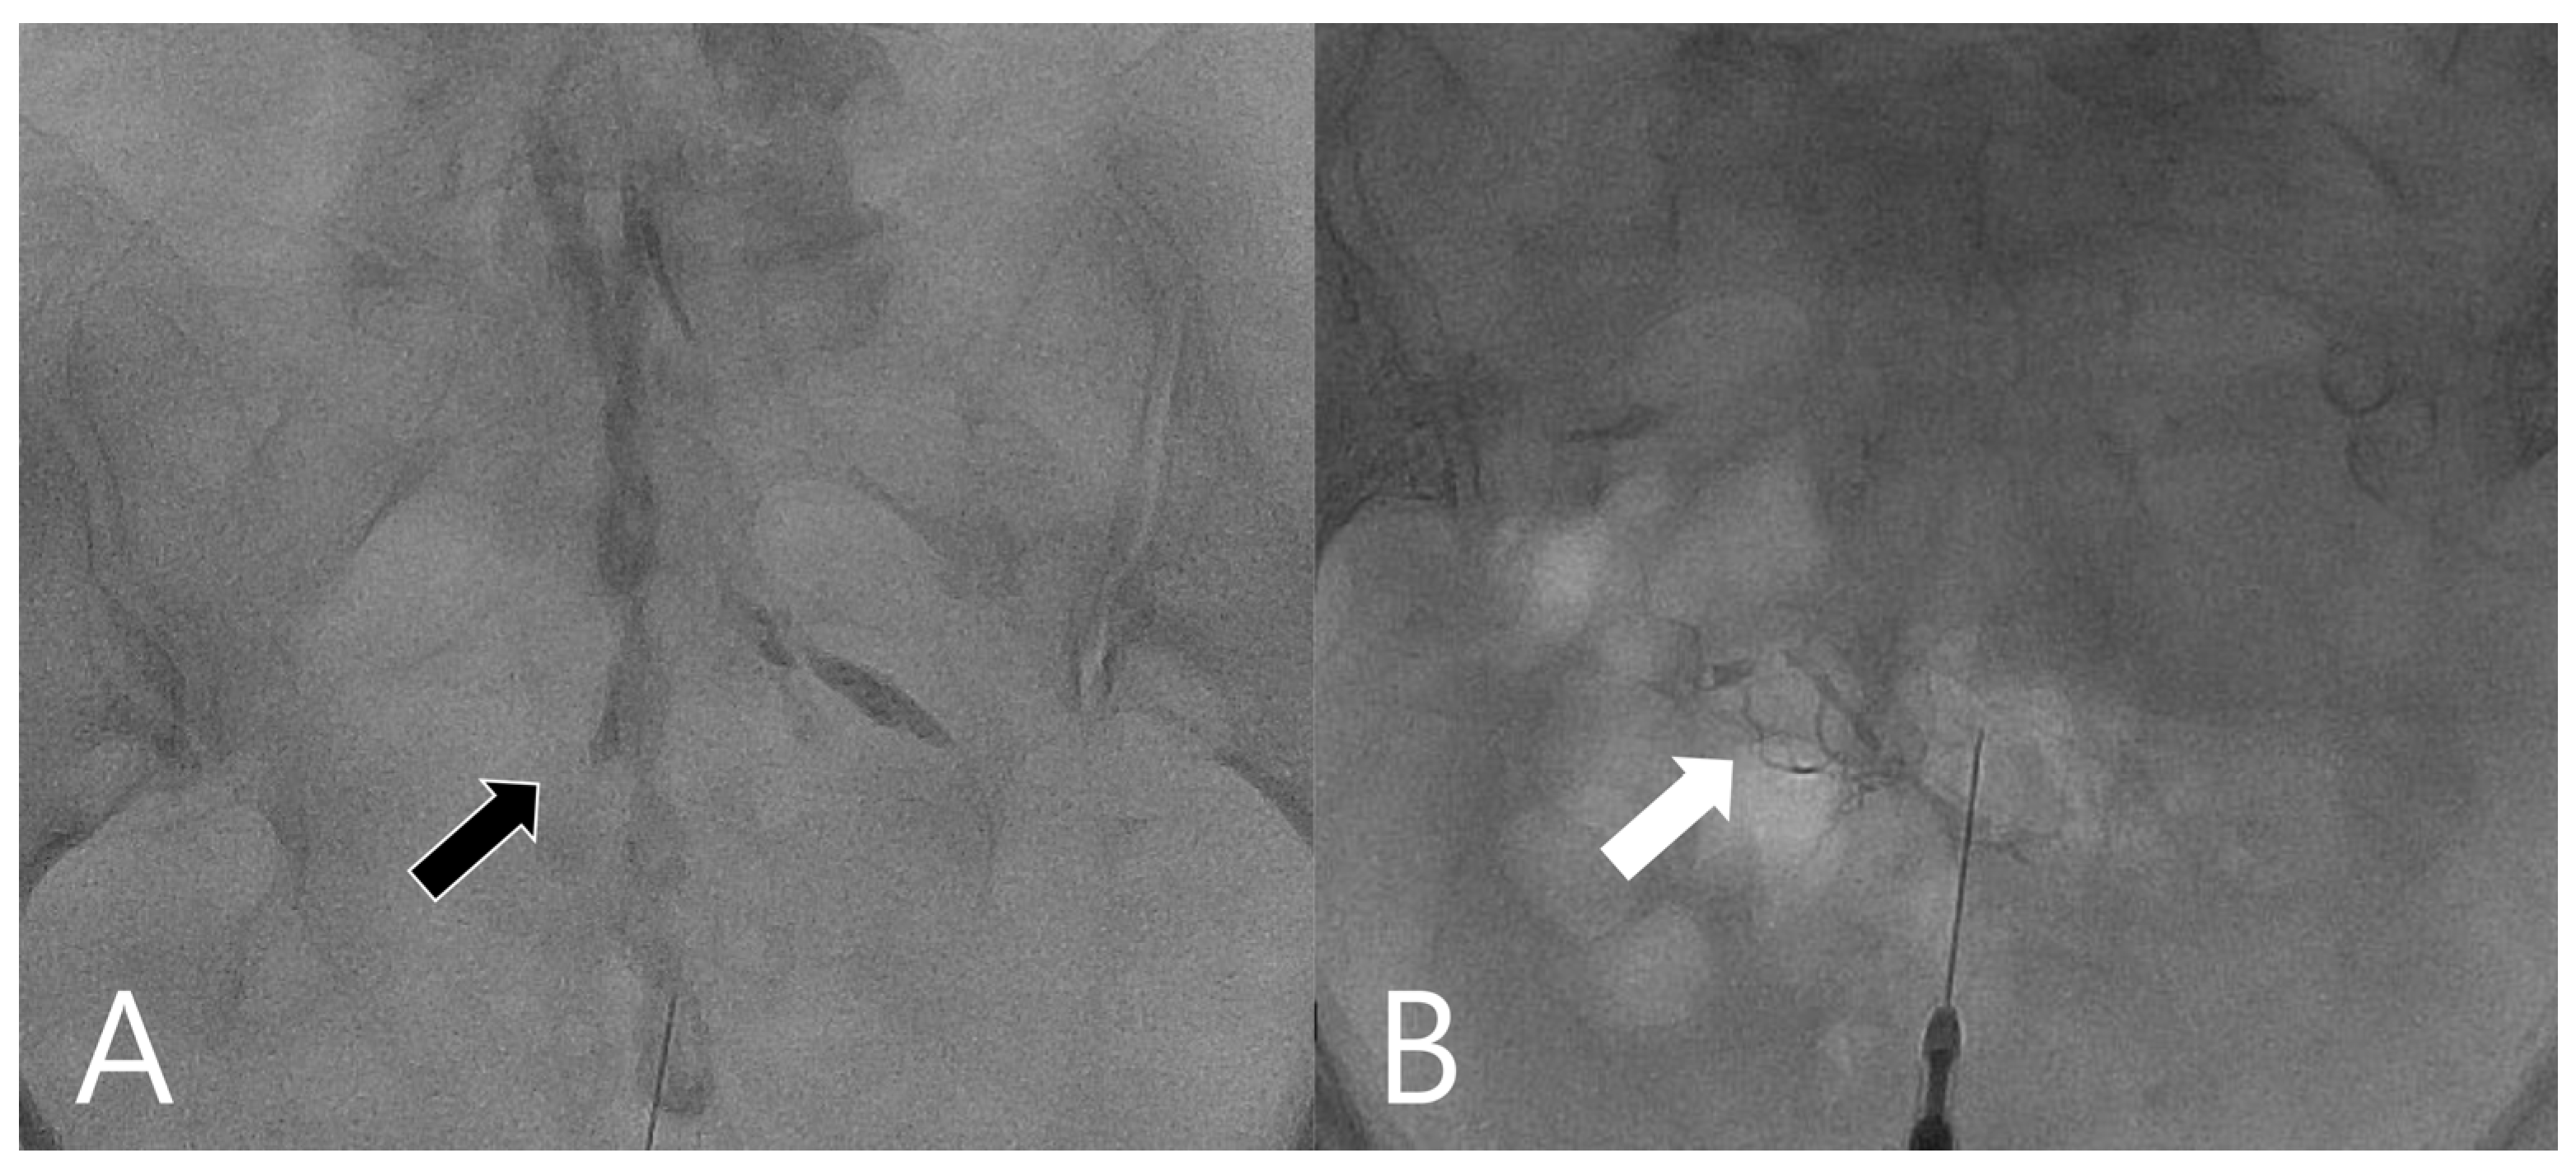

| Flow pattern | <0.001 | ||

| Patch sign | 2 | 237 | |

| Earthworm sign | 7 | 0 | |

| Tubular sign | 0 | 25 | |

| Absent flow | 1 | 5 |

| Earthworm sign | 70 [34.75–93.33] | 100 [98.63–100] | ∞ | 0.3 [0.12–0.77] |